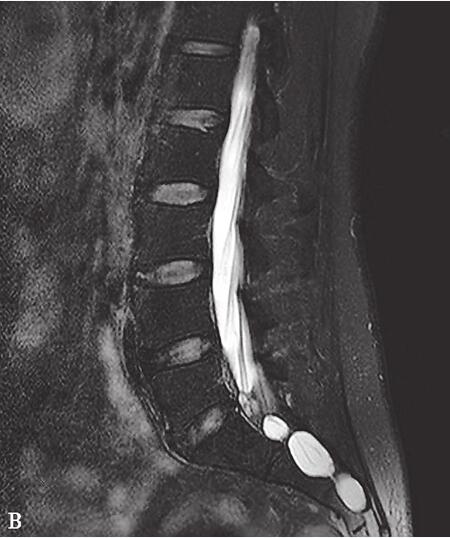

增强腰椎MRI:双侧马尾神经根增粗,明显强化。椎管内可见多发椭圆形液体信号影,边界清楚,增强后囊壁轻度强化。双侧髂腰肌,臀大肌萎缩并脂肪变性。椎间盘未见异常。诊断:双侧马尾神经根炎,骶管囊肿,压迫神经根(图31-2)。肌肉MRI显示:大腿后部肌群萎缩,磷谱提示神经源性肌代谢异常。

图31-2 腰椎MRI增强:轴位T1WI压脂像显示双侧马尾神经根稍增粗,囊壁轻度强化